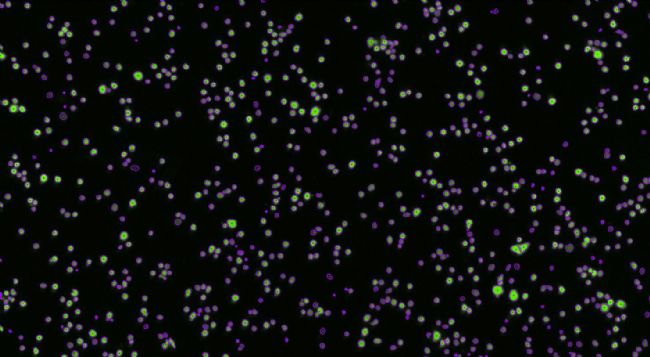

5.Celigo成像

1) 0h靶細(xì)胞全孔圖像 綠色熒光圖像 明場(chǎng)+熒光疊加

2)0h靶細(xì)胞計(jì)數(shù)圖像(取局部圖像)

綠色熒光細(xì)胞圖像 圈定的計(jì)數(shù)的細(xì)胞圖像

3)不同時(shí)間點(diǎn)靶細(xì)胞計(jì)數(shù)圖像

0h 2h 4h 6h

9.不同效應(yīng)時(shí)間點(diǎn)搏殺的細(xì)胞圖像

t=0h

t=2h

t=4h

t=6h